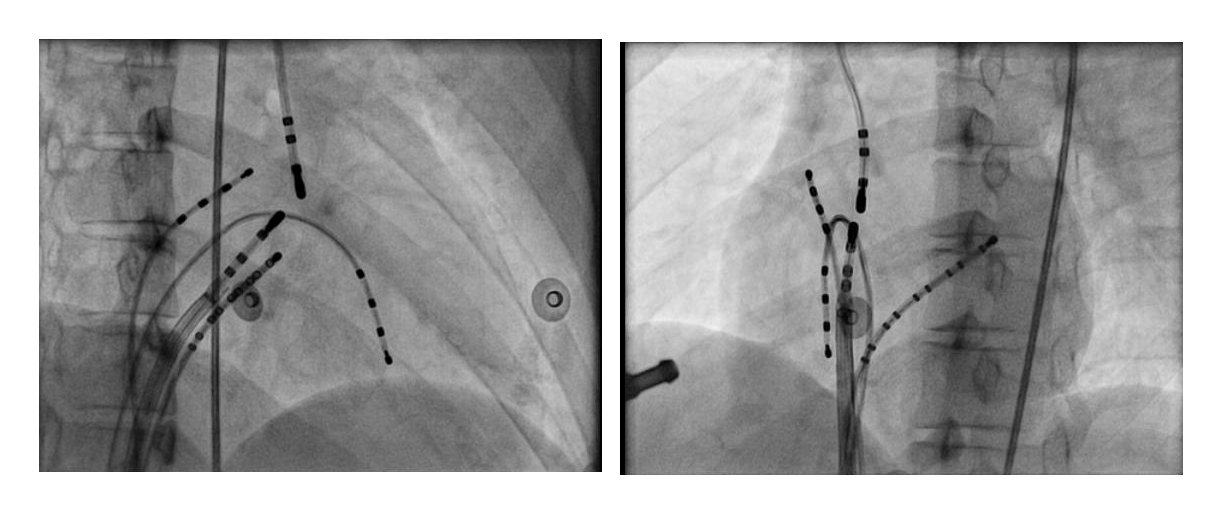

Map and ablate during tachycardia

asap_ablation_tachy.jpg

Anteroseptal AP may be ablated from non coronary cusp

ncc.jpg